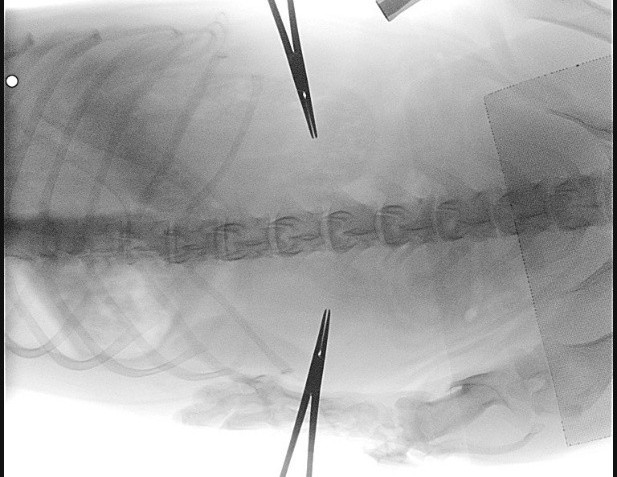

Om vast te stellen of een hond of kat een hernia heeft, voert de dierenarts eerst een lichamelijk en neurologisch onderzoek uit. Daarbij worden reflexen, pijnreacties en spierkracht getest. Voor een definitieve diagnose is altijd beeldvorming nodig: een CT-scan of soms een contrastfoto. Deze onderzoeken laten precies zien waar de hernia zich bevindt en hoe ernstig het ruggenmerg is samengedrukt.

Wanneer een hond ernstige neurologische klachten of verlamming vertoont, is een operatie meestal noodzakelijk. Bij een middenrug hernia maakt de chirurg een opening (sleuf) in de zijkant van de wervel, zodat het uitpuilende tussenwervelschijfmateriaal kan worden verwijderd. Zo verdwijnt de druk op het ruggenmerg. De operatie wordt voorafgegaan door beeldvorming om exact de locatie van de hernia te bepalen.